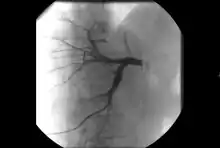

- Angiography: Imaging the blood vessels to look for abnormalities with the use of various contrast media, including iodinated contrast, gadolinium based agents, and CO2 gas.[3]

- Angiography: Sometimes referred to as traditional angiography, catheter angiography or digital subtraction angiography (DSA). A small needle is inserted into a blood vessel, then exchanged for a catheter over a wire. The catheter is directed at the vessel to be studied, and contrast is directly injected to evaluate the lumen under video X-ray. This is an older technique than modern CT angiography or MR angiography, but provides unique advantages. With a catheter in place, provocative maneuvers can be performed such as breath holds or instillation of vasodilators, to evaluate a patient's blood flow dynamically. This can reproduce symptoms and identify functional abnormalities in a vessel that a static CT or MR imaging cannot.[79][80] Angiography provides the basis for all endovascular therapy.